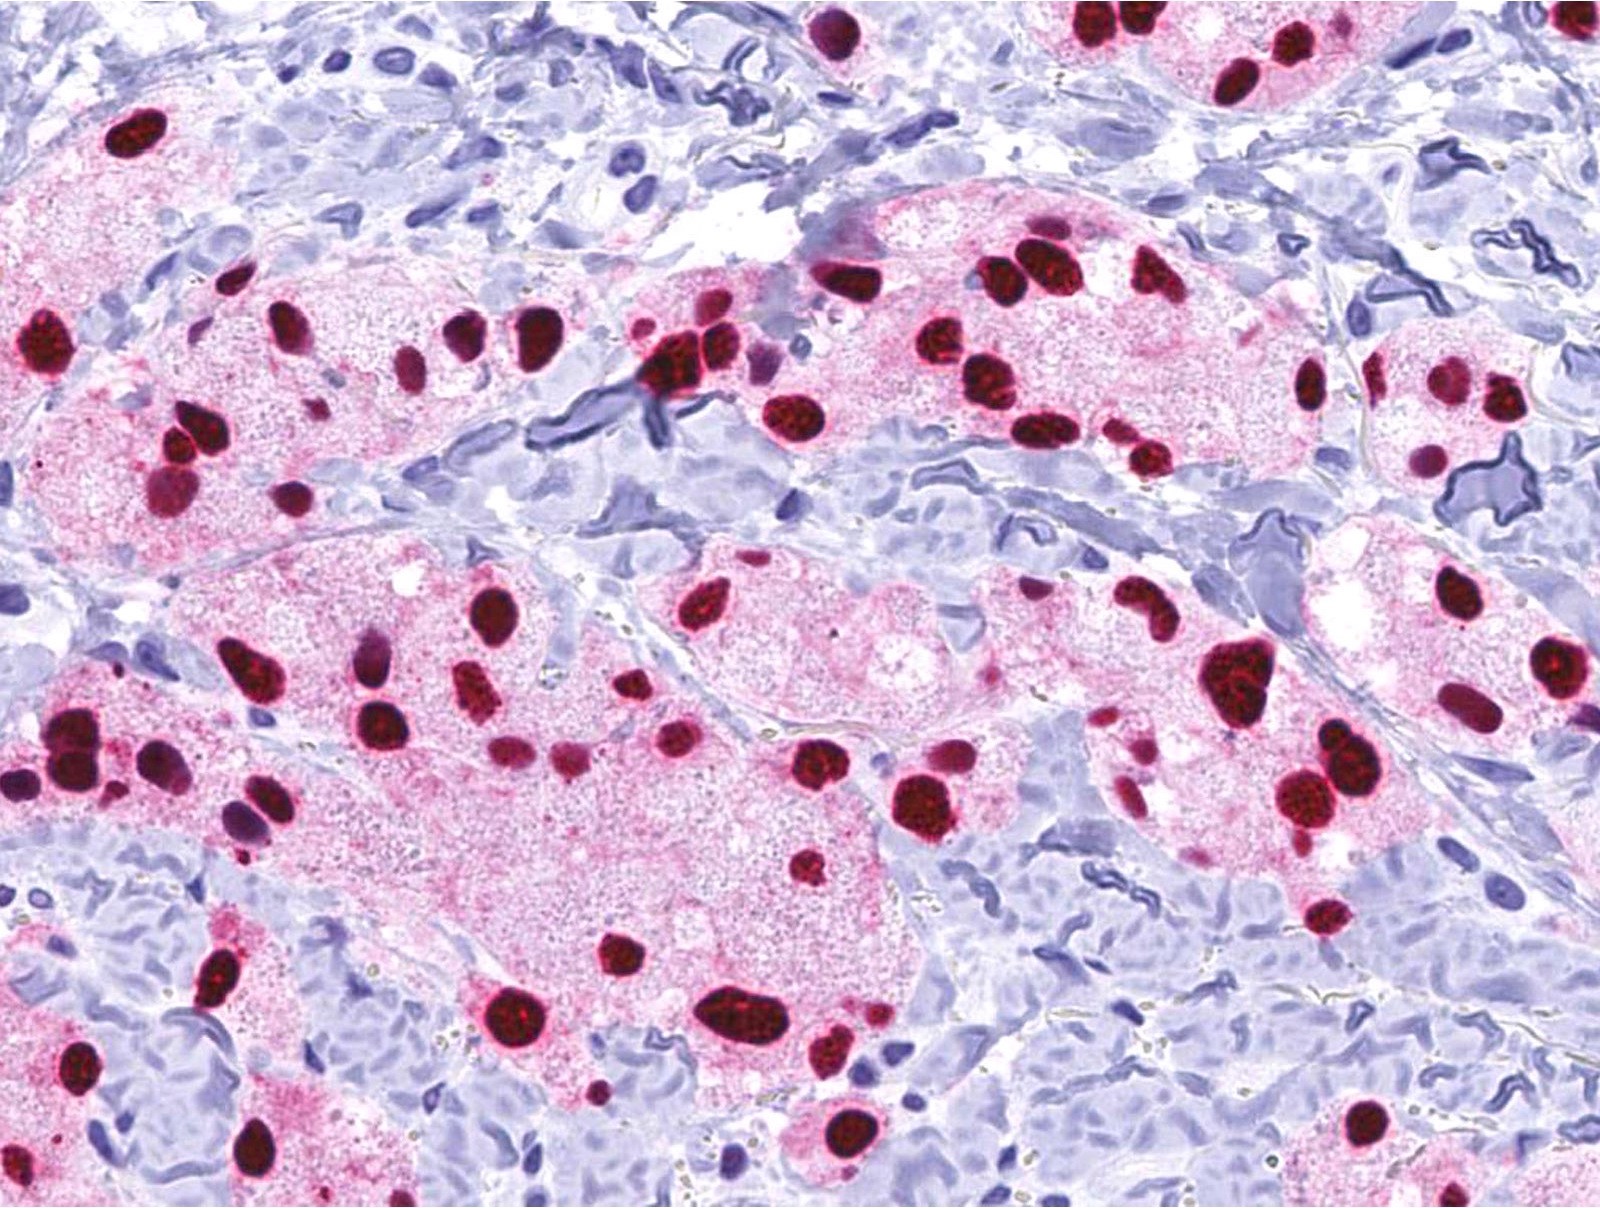

Positive stains

- PASD, Sudan Black B, S100 (except for nonneural granular cell tumors), SOX10, NSE

- Variable staining for vimentin, CD68, NKI-C3 (CD63), MITF, CD56

- A subset of nonneural granular cell tumors express ALK

- References: Cancer 1982;49:1624, Histopathology 2012;61:997, Diagn Histopathol 1982;5:205, Cancer 1989;64:1455, Dermatology 1993;186:106, Am J Dermatopathol 2007;29:22, Hum Pathol 2015;46:813, Am J Surg Pathol 2018;42:1133